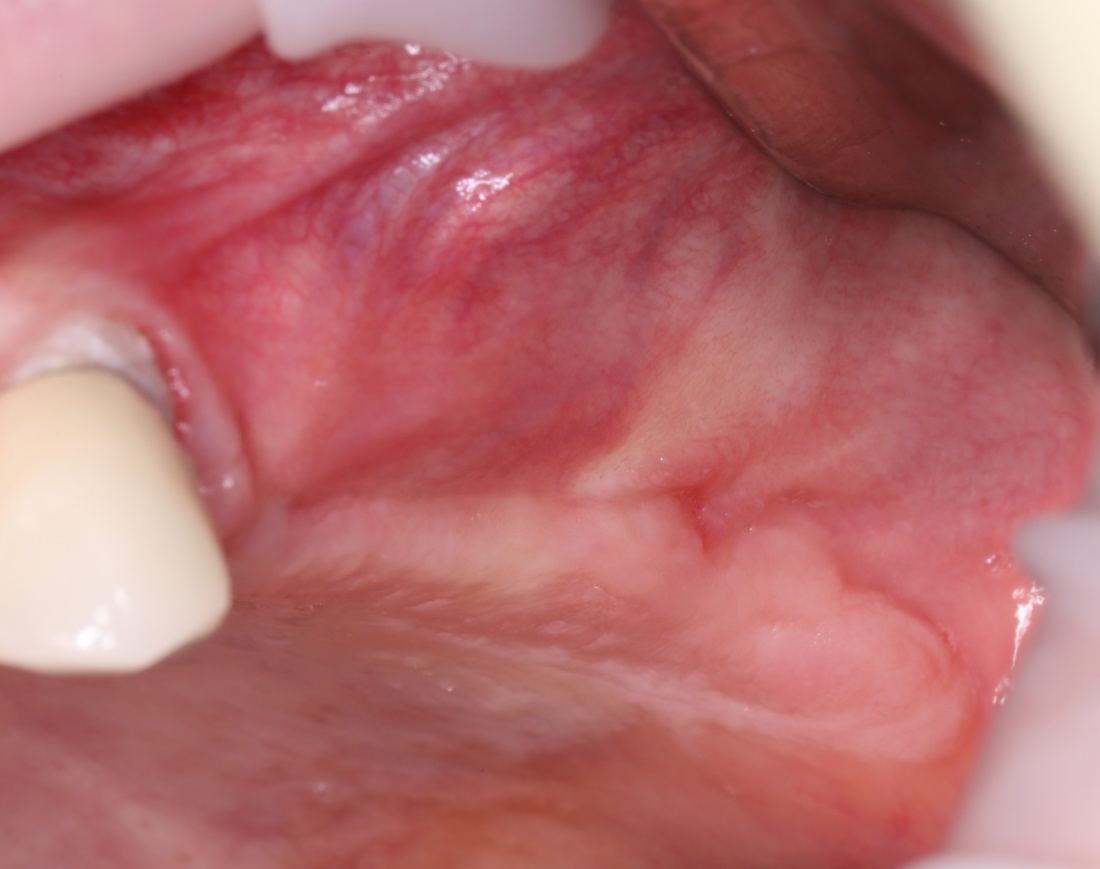

Поэтому после удаления зуба мы ждём, в общей сложности, около 4-8 недель, затем приступаем к имплантологическому лечению. Хотя, иногда бывают ситуации, когда мы делаем синуслифтинг одномоментно с удалением зуба, а сам имплантат ставим попозже:

через 4 месяца: